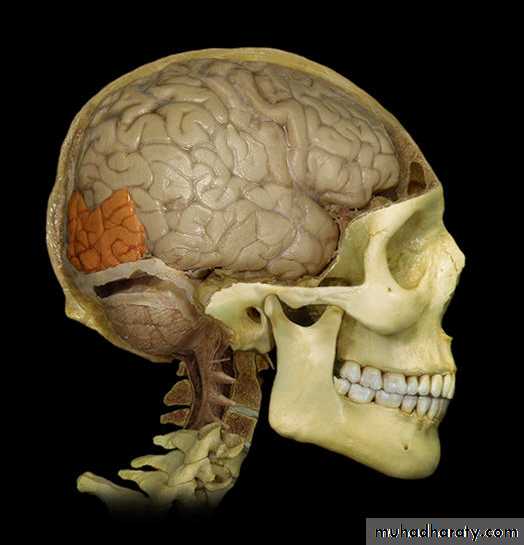

Lobes of Cerebral Hemisphere

Five lobes

Frontal lobe

Parietal lobe

Temporal lobe

Occipital lobe

Insular lobe

Parietal lobeOccipital lobe